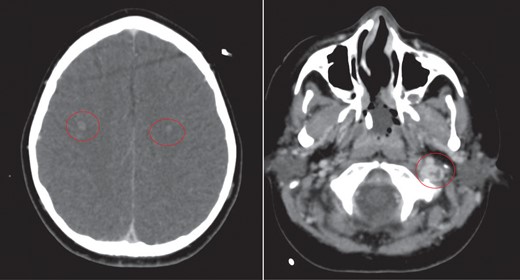

CT of the head with contrast revealed opacification of the left mastoid air cells with multiple ring enhancing abscesses throughout the brain, the largest of which in the left cerebellar hemisphere, measuring 4.4 × 2.9 cm in maximal axial dimensions (Fig. 6). There was non occlusive thrombus of the left internal jugular vein and superior sagittal sinus (Fig. 7). A repeat CT thorax revealed persisting left lung abscesses, a left sided collection and a new post drainage large, right-sided haemothorax.

CT scan of head with contrast revealed multiple ring enhancing lesions within the brain, opacification of the left mastoid air cells and thrombus within the superior sagittal sinus and left internal jugular vein.

The cerebellar brain abscess was drained surgically, with pus sent for microscopy and culture. This returned gram negative coliform organisms and pus cells. The antibiotic therapy was modified to account for the new microbial sensitivities. The appearances of both the brain and chest improved over the next 10 days with complete resolution of the intracerebral abscesses and thrombosis (Fig. 8). There was a slower resolution of the chest. The patient was discharged from our institution after 16 weeks.

Eventual complete resolution of the brain abscesses and sinus/ IJV thrombosis.